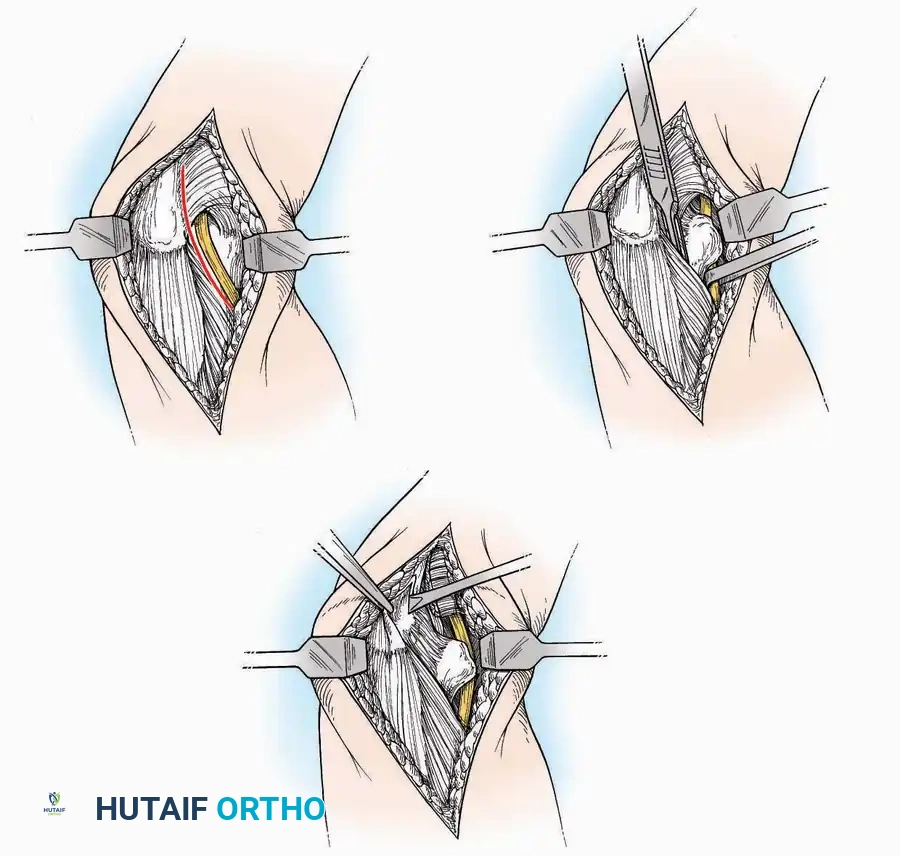

Anterior Approach

Indications: Total ankle arthroplasty (TAA), anterior ankle arthrodesis, and excision of anterior tibial/talar osteophytes (anterior impingement).

Surgical Technique:

* Incision: Make a 10 to 15 cm longitudinal incision over the anterior aspect of the ankle, centered exactly midway between the medial and lateral malleoli.

* Superficial Dissection: Incise the superficial fascia. Identify and protect the superficial peroneal nerve branches laterally and the saphenous nerve medially.

* Internervous Plane: The deep dissection exploits the plane between the Extensor Hallucis Longus (EHL) tendon (innervated by the deep peroneal nerve) and the Extensor Digitorum Longus (EDL) tendons (also innervated by the deep peroneal nerve).

* Neurovascular Bundle: Incise the extensor retinaculum. Carefully identify the anterior tibial artery and the deep peroneal nerve, which typically lie between the EHL and EDL, or directly deep to the EHL. Retract the neurovascular bundle laterally with the EDL, or medially with the EHL, depending on the specific anatomical variant encountered (lateral retraction is most common).

* Capsulotomy: Incise the anterior joint capsule longitudinally. Elevate the capsule subperiosteally from the anterior tibia and the talar neck to expose the entire tibiotalar articulation.